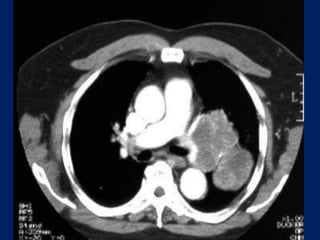

IMAGING

• All patients with suspected NSCLC should undergo

contrast-enhanced computed tomography (CT) that

extends through the lungs, liver, and adrenal glands. CT

is ideal for tumor node metastasis (TNM) staging

• It can characterize the primary tumor and define its

relationship to the chest wall and mediastinal

structures

• It can identify mediastinal lymph nodes that are

enlarged and suspicious for malignant involvement

• It can detect contralateral lung, chest wall, or upper

abdominal lesions that are suspicious for metastasis